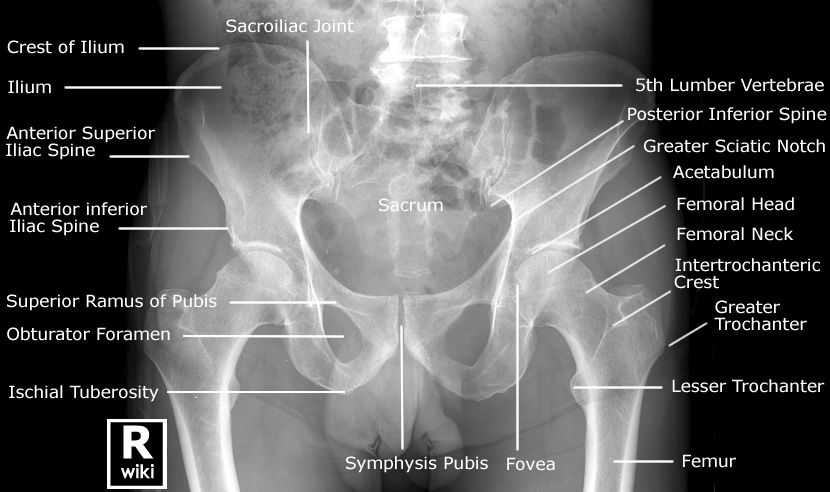

| [Anatomy] Hip joint(고관절) (0) | 2024.01.29 |